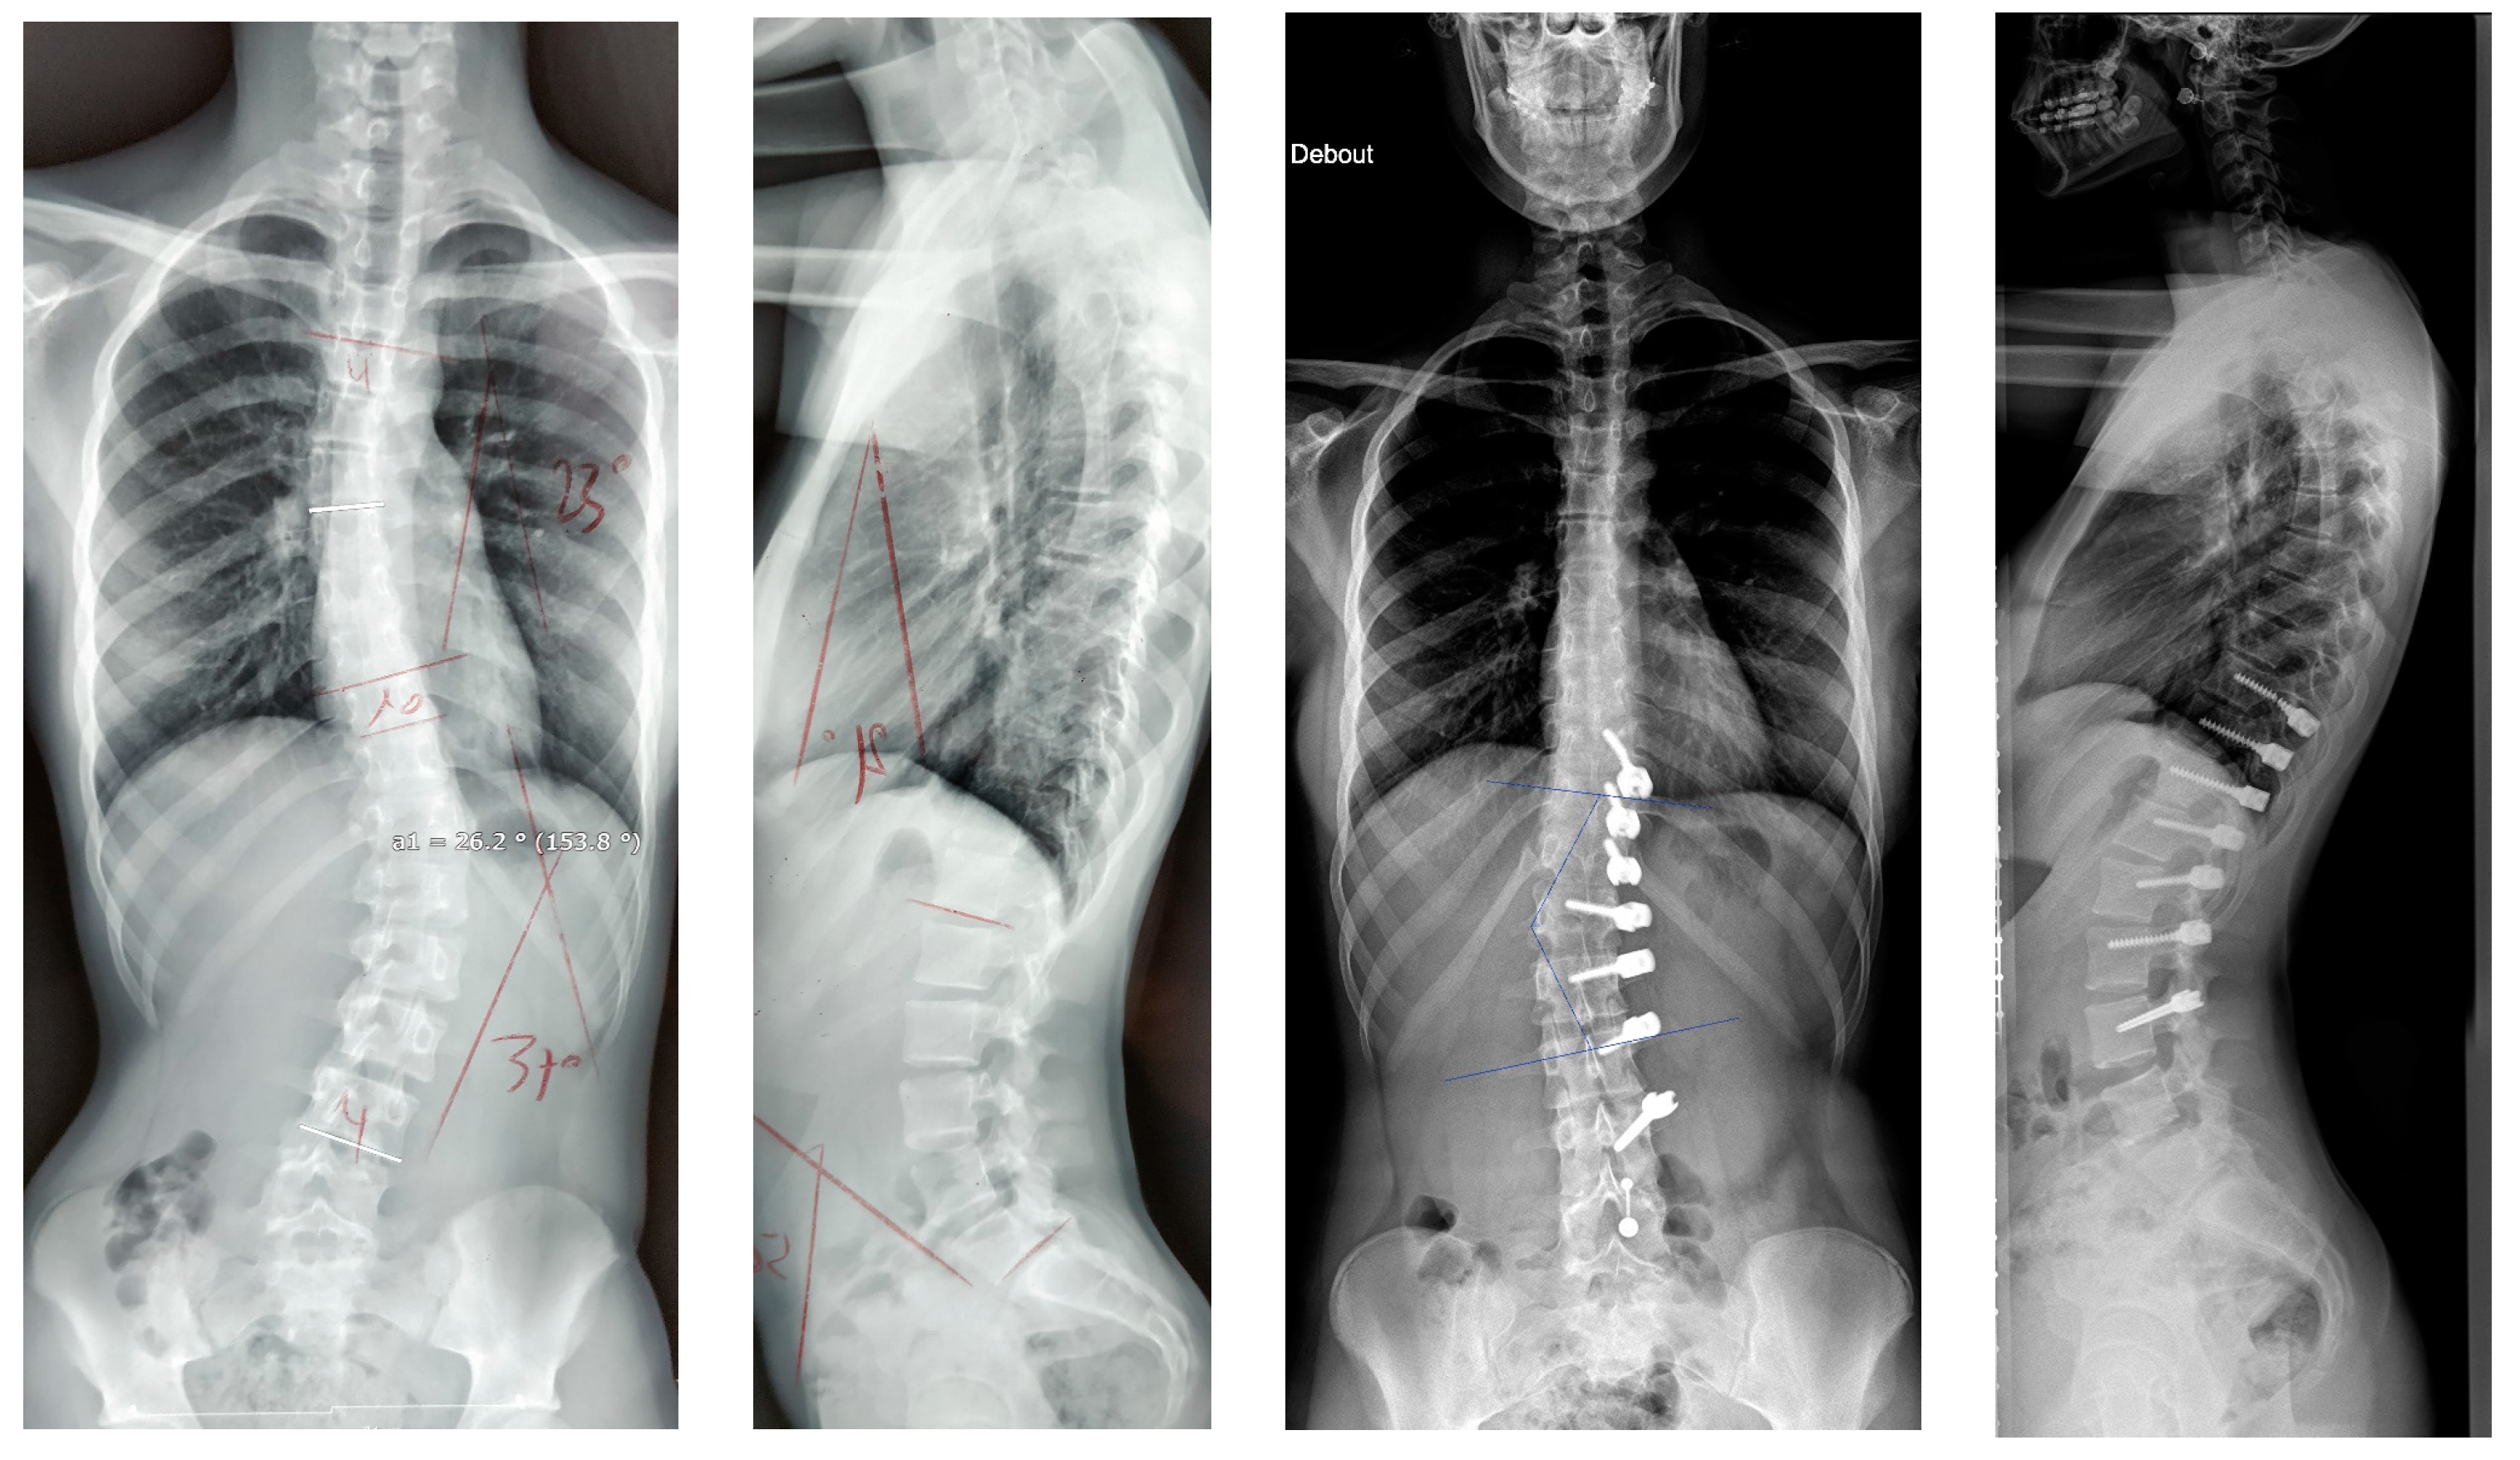

If we analyse the correction and look first at the results after surgery and before, there was an initial improvement of the major curve from 43.9° to 20.3° (54%) due to the “brace effect”, as was observed in other studies [1]. But if we compare the results after surgery and at two years (Figure 7), it seems there was not much correction by growth modulation as described in Anterior Vertebral Body Tethering [1,17,18]. Indeed, there was an amelioration of 7.1° (35%), but it was not statistically significant. This result was unexpected, and must be investigate with studies involving more patients as there was clearly a growth modulation on several cases, leading to an overcorrection. An explanation could be the average old age of the patients with not enough growth remaining.

Figure 7.

A 13-year-old female, Risser 0. The lumbar curve measured 38° pre-operatively, improved to −10° (slight overcorrection) at two years. In this case, there was an augmentation of both the lumbar lordosis (40° to 58°) and thoracic kyphosis (22° to 37°).